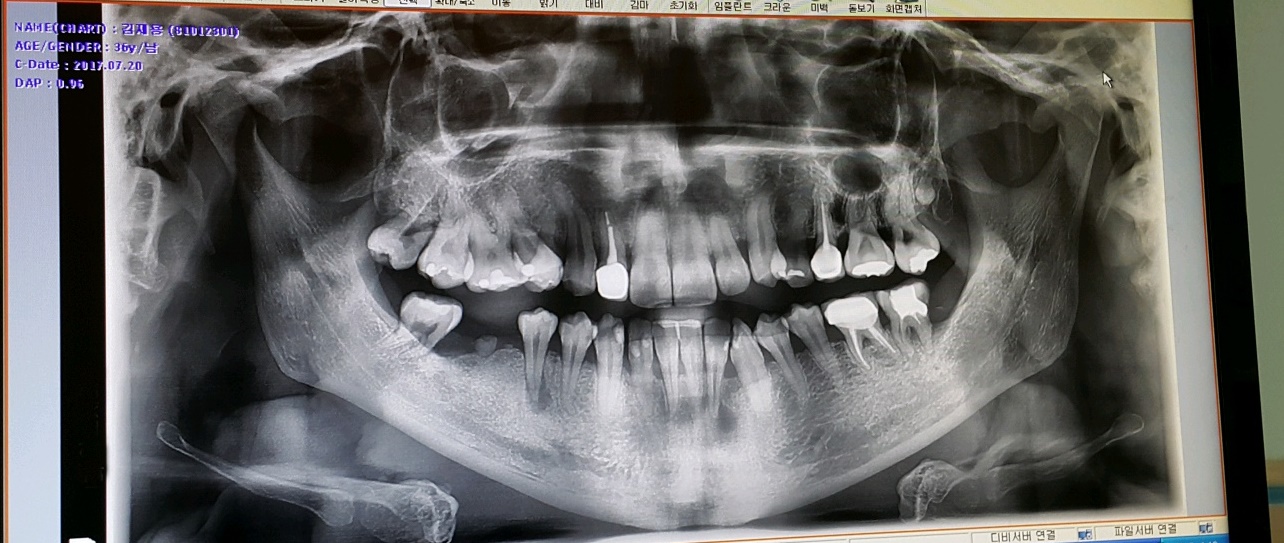

3년전 부정교합 시작하기 전의 내 치아 상태는 지금 생각해 보면 정말 최악?? 이였다.. 썩은치아와, 부정교합으로 인해 삐뚤어진 치아들... 그러다 주걱턱 교정 때문에 강남의 비수술 교정치과를

내 치아 상태는 위아래의 부정교합(이~ 했을 때 보통 사람들과는 조금 틀리게 밑의 치아가 윗 치아들을 덮는 반대교합)이 아주~ 심한 정도까지는 아니여도 그냥 보기에도 주걱턱이 확연히 들어나 있는 상황 이였다.

이제 교정이 끝나갈 무렵 어렸을 때(중딩시절) 주걱턱 교정 때문에 발치를 해야했던 하악 오른쪽 작은 어금니의 임플란트를 할 시기가 왔다...

해서 바로 시술 하려 했으나 양쪽해서 2개 박는데 320만원.... 거기다 뼈이식까지 포함하면 360;; 생각 했던 것 보다 가격이 많이 부담스러운 찰나 기억이 가물가물 한 치과에서 문자가 왔는데 임플란트 1개당 기본 76만원...? 상당히 파격적인 가격이라 방문하게 되었고, 상담결과 2개가 아닌 4개를 해야될 수도 있다고 한다;;

이유인즉슨 치아들끼리 양 옆으로 지탱해줘야 서로 튼튼한데 오른쪽 작은어금니를 뽑은지 너무 오래된 상태라(중딩때 주걱턱 교정때문에 멀쩡한 치아를 발치했었음) 어금니 뿌리가 잇몸에 살짝 걸쳐진 상태였고 치아교정때문에 부득이하게 치아가 하나 없는 상태임에도 와이어를 달고 무리하게 당겼기에 옆으로 임플란트를 하나 박는다 해도 어금니는 얼마못가 못쓰게 되서 뽑아야 된다고 한다.